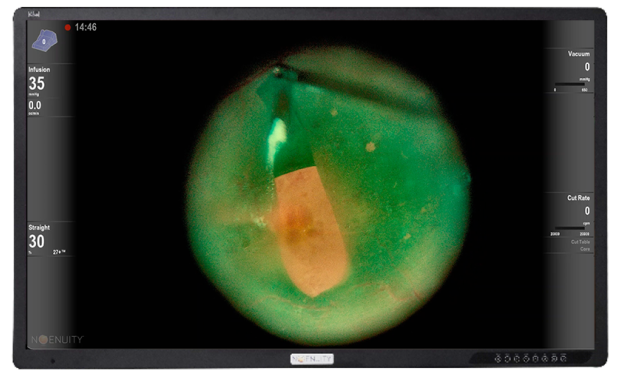

CONSTELLATION® DATAFUSION

A Centralized View, Tailored to You – CONSTELLATION® DATAFUSION delivers a real-time view of surgical parameters and system performance providing more information during critical surgical steps, allowing you to keep your eyes on what's most important.8

Custom image profile

Link your CONSTELLATION® procedural steps with your preferred image modes for greater efficiency and enhanced visualization at every step.2,13,14